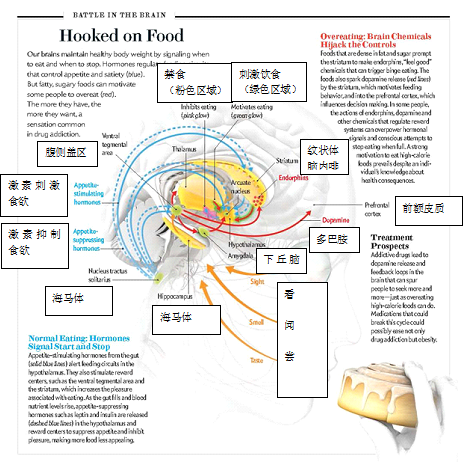

或许当功能型插画较传统的解剖图更容易被人们的接受时,我才能够与这个工作组进行十分默契的合作。其他多位演讲者的讲座内容让我明白,解剖学插图已经不仅仅是传统的那样,的确,它应该充满生命力,且绝对切题。但是我还是渴望看到超出具象的视觉交流。数据可视化和/或新的信息化插图形式在哪里?(我应该缓和文本中的用词。正如我之前所提及的那样,许多数据可视化的工作并没有得到重视,或者只是在手术训练和医疗案件起诉这种解剖学至上,具象的插图至上的事件中被用到。其他几人,如Lisa Nilsson 和 Travis Vermilye的报告,正在利用医药激发灵感的美术来开发新的可视化形式)

但是,我不得不说——整个学术领域进步影响着我们对插图的想法。比如,当神经学家离绘制整个大脑更进一步时,我们就会愈发摒弃对大脑的具象描写吗?数据的输入(源于人类大脑计划这样的活动)能够从根本上改变我们绘制大脑的方式吗?

而对大脑的质化描绘会是这样吗?。

图片来自2011年3月《科学美国人》“勇气的神经科学”一文,作者:Gray Stix,插图作者:Jen Christiansen。

当插图由粗糙的卡通风格转变为精确的电子数据风格,对我而言,似乎我们能做的比这个更少:

图片来自2013年9月《科学美国人》“食物上瘾”一文,作者:Paul J. Kenny,插图作者:Bryan Christie。

但是对于一份大众杂志而言,有时用抽象的形式描述信息比局限性地用更加令人熟知却没有更加全面的信息的方式更有效。特别是当人们试图描述一个十分特定课题中的特殊部分时更是如此。诀窍在于利用受欢迎的方式来让图片变得更加亲切——我们可以用简洁的关键词和释文吸引读者,并让他们更清楚地了解里面的内容。